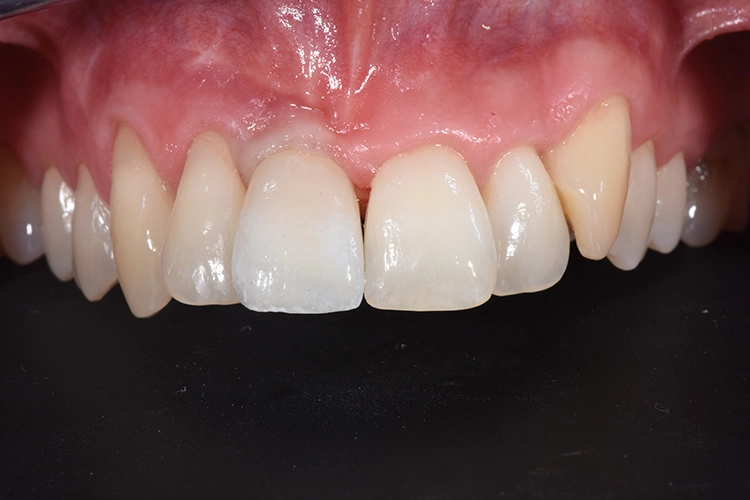

Für die Herstellung des Provisoriums wird die Zahnkrone zunächst von Granulationsgewebe befreit, anschließend mithilfe rotierender Instrumente und dem Sandstrahlgerät gereinigt und für die adhäsive Verbindung mit dem PEEK-Aufbau vorbereitet. Intraoral wird die Zahnkrone mit dem provisorischen Abutment verklebt.

Die erste Verbindung dient ausschließlich der dreidimensionalen Fixierung in Relation zum Abutment. Die weitere Ausarbeitung der Krone erfolgt extraoral, wobei auf die Gestaltung eines physiologischen Emergenzprofils geachtet werden muss. Anschließend wird das Provisorium einfach auf die Implantat-Basis geklickt, das Bild zeigt die Situation unmittelbar nach der Implantation (Abb. 23-28).